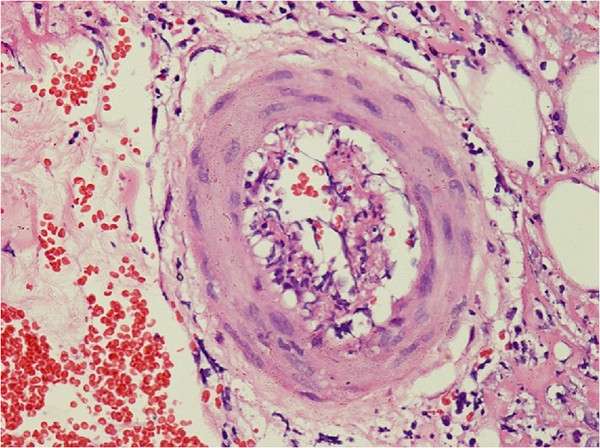

El diagnóstico de poliarteritis nodosa requiere una confirmación mediante técnicas de imagen o biopsias de los tejidos afectados. Las biopsias de los sitios sintomáticos, como la piel, los nervios o los músculos, son esenciales para confirmar la enfermedad. Es particularmente importante realizar una biopsia profunda de las úlceras cutáneas o de los nódulos en la piel, en lugar de una biopsia por punción, para asegurarse de que el vaso sanguíneo de tamaño medio esté incluido en la muestra, ya que la afectación de estos vasos es característica de la enfermedad. En los pacientes que presentan síntomas neuropáticos, las pautas actuales recomiendan realizar biopsias tanto del nervio como del músculo, en lugar de una biopsia de solo nervio, para obtener una muestra más representativa de la afectación de los nervios periféricos.